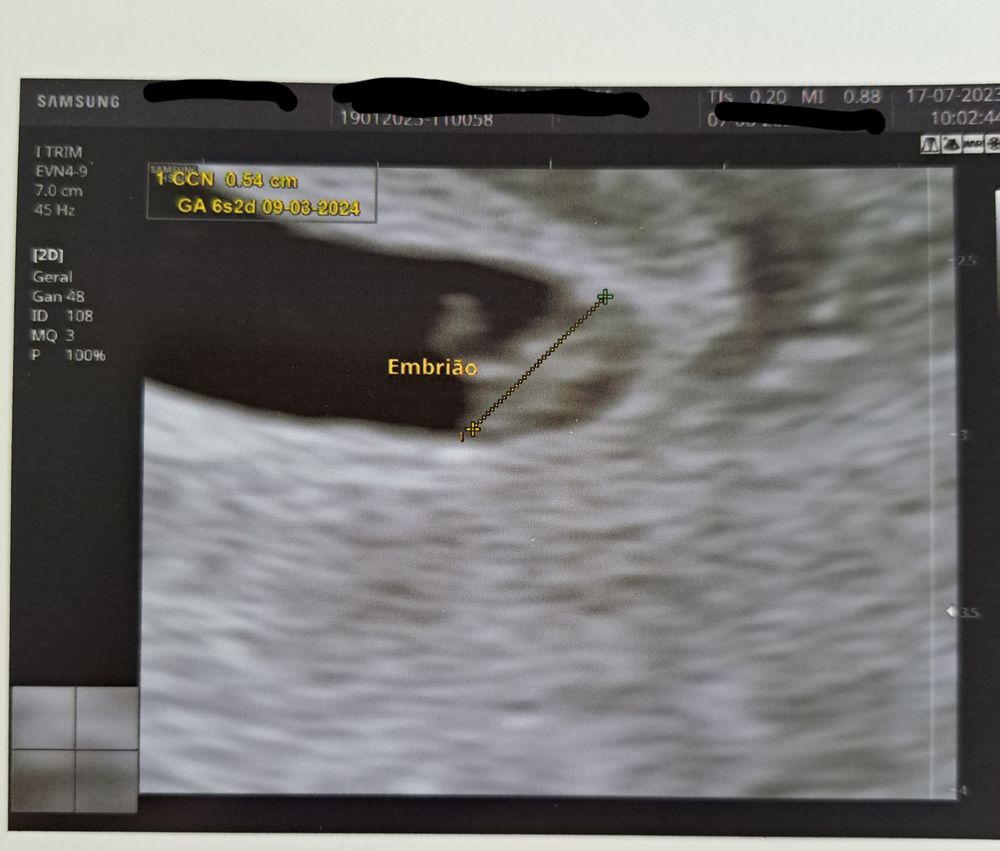

26 ДПП и наше первое узи👶

Blanca, спасибо😍! До сих пор не верю, но теперь у меня есть доказательства 😁